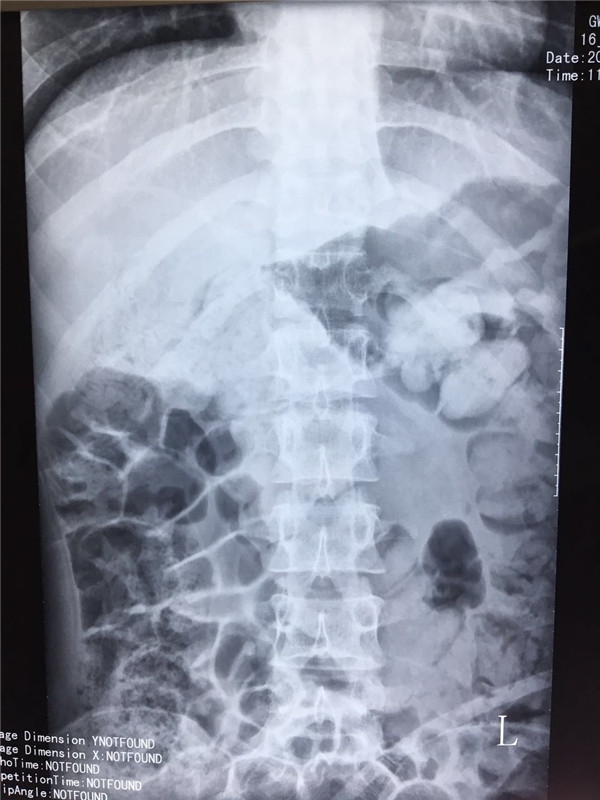

术前 正位